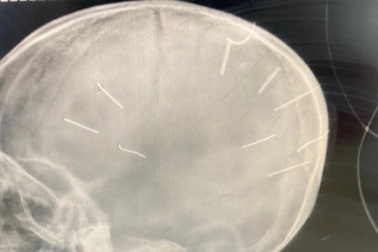

01:00 11/08/2025 GMT+7

Ông Đặng Hoa Nam, Cục trưởng Cục trẻ em xác nhận, tổng đài điện thoại quốc gia bảo vệ trẻ em (số 111) nhận cuộc gọi từ người thân của bé gái bị cắm đinh vào đầu yêu cầu hỗ trợ và đã vào cuộc ngay. Vụ anh em đuối nước ở Hà Nội: Có nên lấp giếng làng để an toàn?